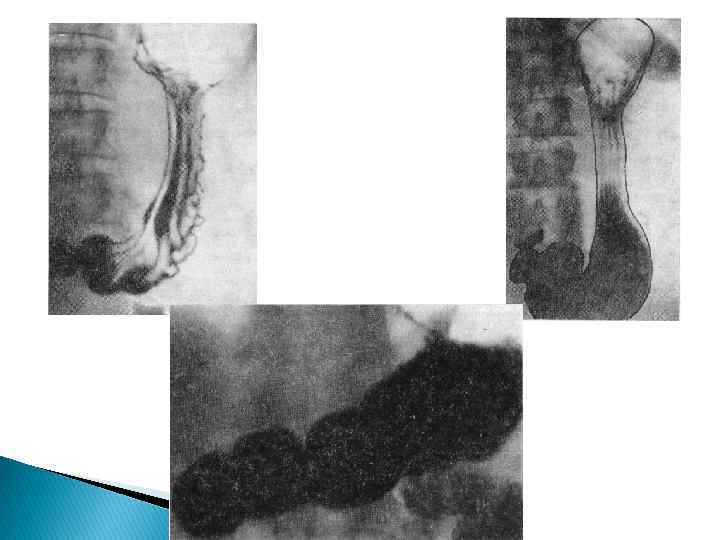

Рентгенологическая норма Гортанное сужение ППП Аортальное и бронхиальное сужения ППП ПКП

Диафрагмальное и кардиальное сужения пищевода